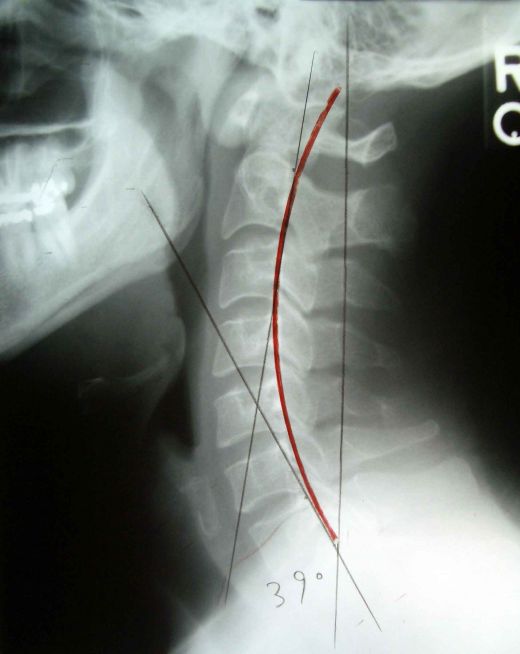

And this simulates quite nicely how my x-ray looked:

This is known as “reverse curve” and also as “forward head”.